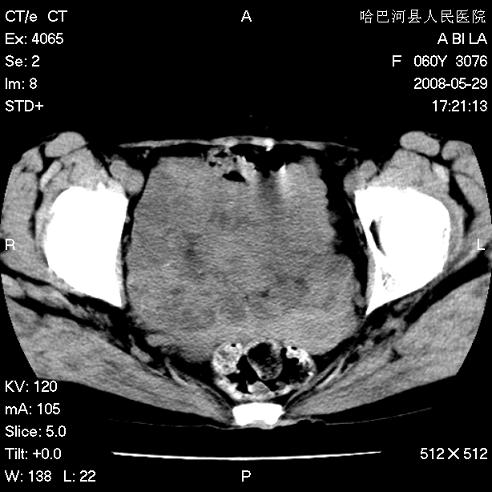

标题: CT13730:排尿不畅4天,抗炎治疗无效,现尿中可见血块 [打印本页]

标题: CT13730:排尿不畅4天,抗炎治疗无效,现尿中可见血块

膀胱癌伴转移。 支持。

手术结果及病理:膀胱癌并膀胱壁转移,膀胱内血块